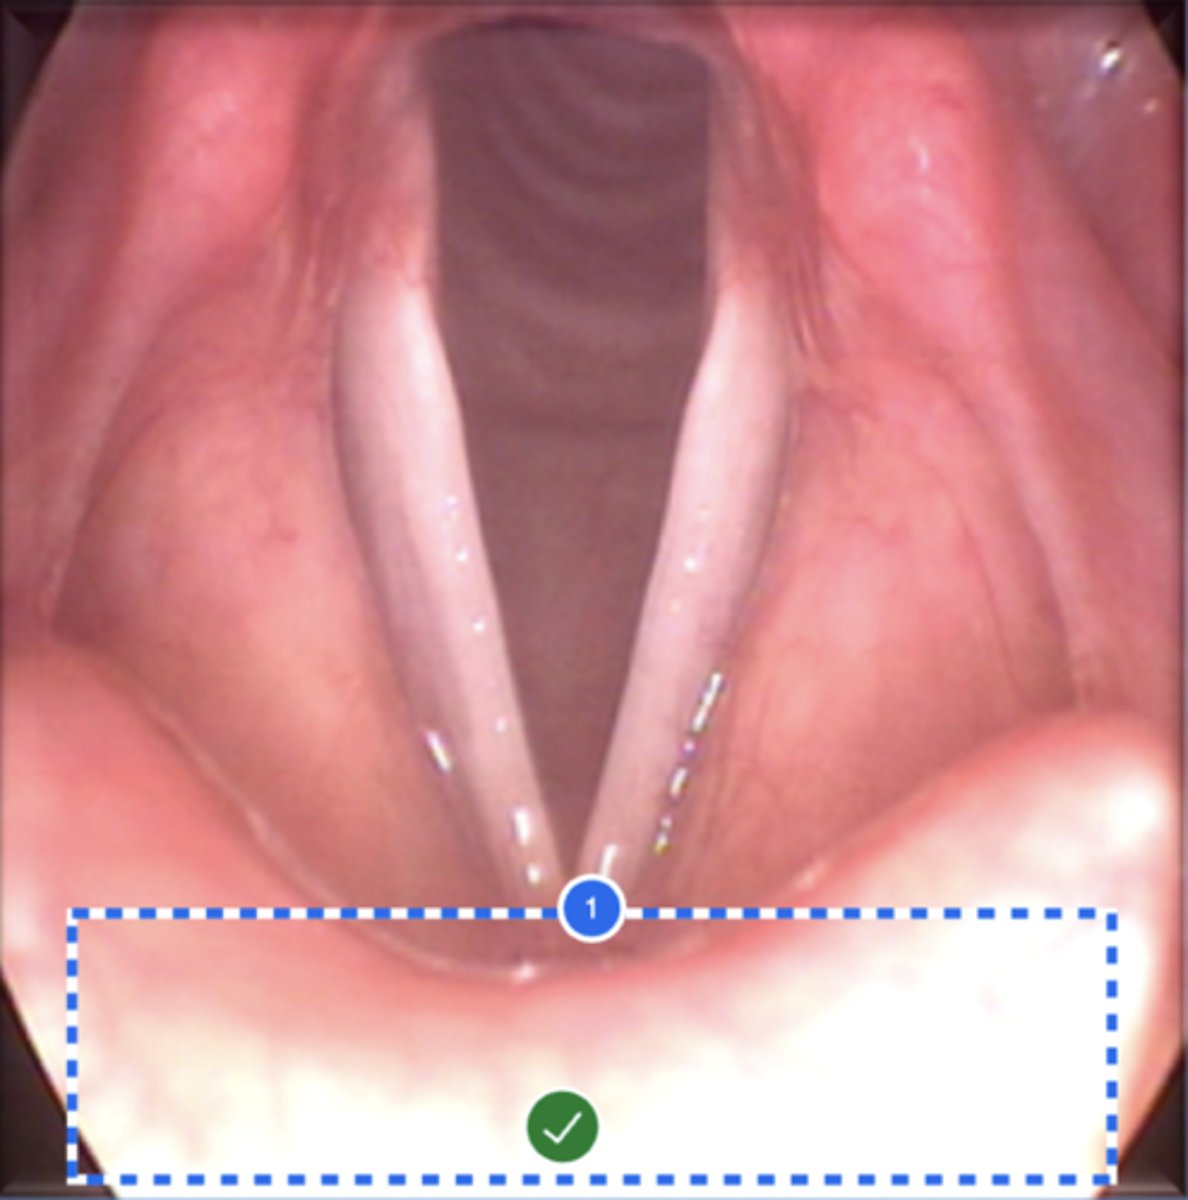

Label left true vocal fold (superior view)

Label right false vocal fold (superior view)

label right arytenoid (superior view)

Label trachea (superior view)

Label epiglottis (superior view)

Label left aryepiglottic fold (superior view)

Label laryngral surface of epiglottis (superior view)

Label lingual surface of epiglottis (superior view)

Label base of tongue (superior view)

Label right pyriform sinus (superior view)

Label upper esophageal sphincter (superior view)

Label right true vf (superior view)